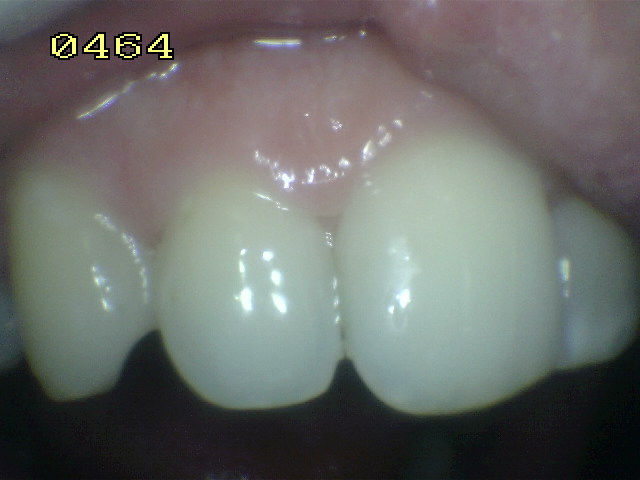

El diente al lavarse y secarse con la jeringa triple deja expuesto esmalte blanquecino escarchado o opaco que delata un proceso de desmineralización, debido a que el agua se evapora de los microporos. Ver círculos rojos